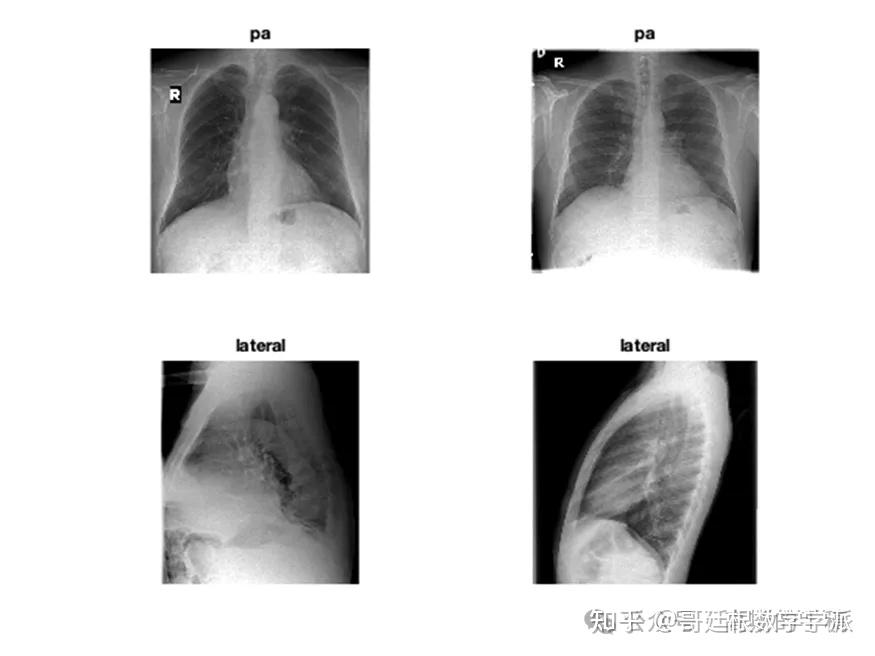

医学图像的深度学习可解释性(MATLAB R2021B)